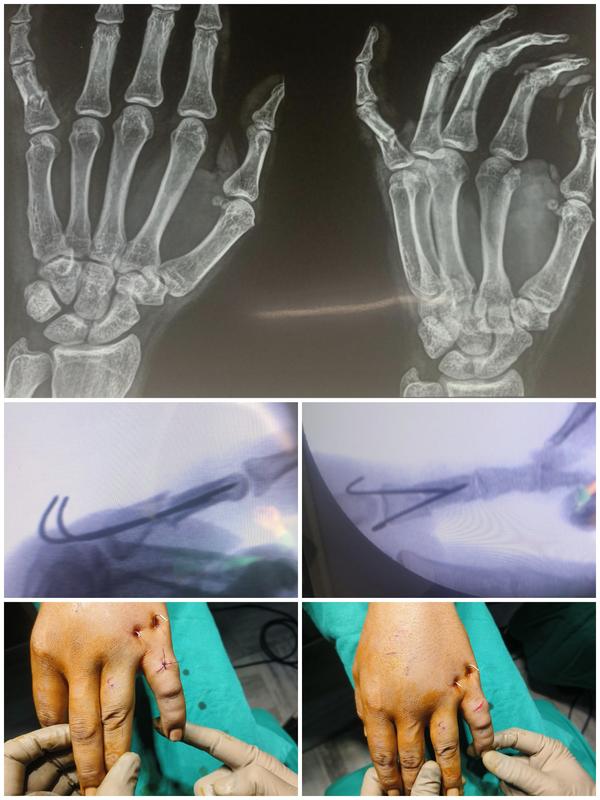

34 year old labour sustained injury to left little...